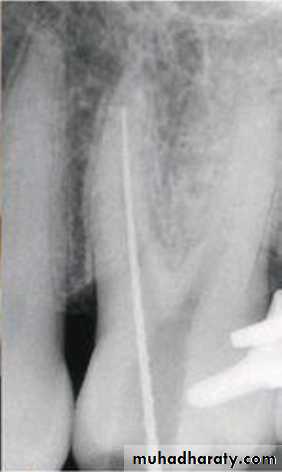

Step-Down Technique

The step-down technique is advocated for cleaning and shaping procedures as it removes coronal interferences and provides coronal taper.

With the pulp chamber filled with irrigant or lubricant, the canal is explored with a small instrument to assess patency and morphology (curvature). The working length can be established at this time.

The coronal one third of the canal is then flared with Gates-Glidden drills or rotary files of greater taper (.06, .08, or .10).

A large file (such as No. 70) is then placed in the canal, and a watch-winding motion is used until resistance is encountered.

The process is repeated with sequentially smaller files until the apical portion of the canal is reached. The working length is checked again.

The apical portion of the canal can now be prepared by enlarging the canal at the corrected working length.